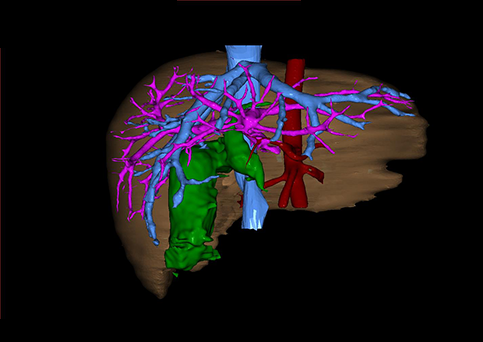

10、三维重建虚拟肝脏、胆道显像技术

三维虚拟肝脏技术是在二维影像学资料如CT等图像的基础上,通过三维重组软件和工具,比如青岛大学附属医院与海信医疗集团联合自主研发的海信计算机辅助手术系统(Hisense Computer Assisted Surgery,Hisense CAS),目前已投入临床并指导实际应用,利用该类系统对二维影像学的数据资料进行三维立体分析,重组形成立体的、有空间结构的、虚拟的肝脏三维图像。这项技术较传统的二维平面成像技术,有着明显的优势,3D虚拟肝脏技术可以构造出一个虚拟的、可视化的肝脏模型。通过对这种模型的观察,可以很容易地分辨出肝脏器官的组织结构、解剖特点,直观研究肝外胆总管的形态差异,明确肝内胆管的形态、走形、是否合并扩张、狭窄及结石,胰胆管合流的形态及共同通道内是否有狭窄、扩张和结石等病变情况,预先规划处理可能合并存在的肝内胆管扩张、狭窄或其他复杂胆道畸形,清晰地显示肝内脉管系统,包括门静脉、肝动脉及肝静脉的走行、分支,并可多角度、全方位观察病变胆道与其周围重要血管尤其是伴行的门静脉之间的解剖关系,大大提高了外科医师在术前对肝脏内部各管道结构及其变异判断的精确性和可靠性,精准地对病变进行判断和评估,还可根据患者自身的病变特点,制定出合理、个体化的手术方案,最大限度地降低术中和术后并发症发生率,并术中导航实时指导手术,提高手术的精准性和成功率。

图10:先天性胆管扩张症囊肿型三维重建虚拟肝脏、胆道显像

a 图为术前二维CT扫描图像,箭头所示为肝内胆管扩张;b 图为CT经多平面重组技术(MPR)图像后处理所得的重建图像,可显示胆总管明显扩张合并肝内胆管扩张;c 图为MRCP显示胆总管呈囊柱状扩张,直径>1 0 cm,伴肝内胆管扩张;d 图示Hisense CAS三维重建清晰显示肝脏、胆道系统及其与门静脉、肝动脉、肝静脉等之间的空间解剖关系;e 图示Hisense CAS可从任意角度以不同脏器组合显示,明确胆道系统与其伴行的门静脉系统的空间解剖关系;f 图示胆道系统立体形态及与肝脏整体的空间关系,箭头处显示肝内胆管狭窄部位发生于左右肝管汇入肝总管处。术前规划需行肝内胆管扩大成形术。